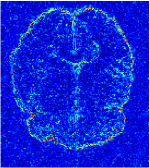

All the experiments are implemented on a Windows workstation with Intel Core i9 CPU at 3.3GHz and an Nvidia GTX-1080Ti GPU with 11GB of graphics card memory via TensorFlow Abadi et al. (2016). The parameters in the proposed network are initialized by using Xavier initialization Glorot and Bengio (2010). We trained the meta-learning network with four tasks synergistically associated with four different CS ratios: 10%, 20%, 30%, and 40%, and test the well-trained model on the testing dataset with the same masks of these four ratios. We have 300 training data for each CS ratio, which amount to total of 1200 images in the training dataset. The results for and MR reconstructions are shown in Tables 5.4 and 5.4 respectively. The associated reconstructed images are displayed in Figures 1 and 3. We also test the well-trained meta-learning model on unseen tasks with radio masks for skewed ratios: 15%, 25%, 35%, and random Cartesian masks with ratios 10%, 20%, 30% and 40%. The task-specific parameter for the unseen tasks are retrained for different masks with different sampling ratios individually with fixed task-invariant parameters . In this experiments, we only need to learn for three skewed CS ratios with radio mask and four regular CS ratios with Cartesian masks. The experimental training proceed on less data and iterations, where we performed on 100 MR images with 50 epochs. For example, for reconstructing MR images with CS ratio 15% radio mask, we fix the parameter and retrain the task-specific parameter on 100 raw data with 50 epochs, then test with renewed on our testing data set with raw measurement that sampled from radio mask with CS ratio 15%. The results associated with radio masks are shown in Table 5.4 and 5.4, Figure 2 and 4 for and images respectively. The results associated with Cartesian masks are list in Table 5.4 and reconstructed images are displayed in Figure 5.

Qualitative comparison between conventional and Meta-learning methods are shown in Figure 1 and 3, which display the reconstructed MR images of the same slice for T1 and T2 respectively, we label the zoomed-in details of HGG in the red boxes. We observe the evidence that conventional learning is more blurry and lost sharp edges, especially in lower CS ratios. From the point-wise error map, we find meta-learning has the ability to reduce noises especially in some detailed and complicated regions comparing to conventional learning.

In this section, we test the generalizability of the proposed model that tests on unseen tasks. We fix the well-trained task-invariant parameter and only train for sampling ratios 15%, 25% and 35% with radio masks and sampling ratios 10%, 20%, 30% and 40% with Cartesian masks. In this experiment, we only used 100 training data for each CS ratio and apply a total of 50 epochs. The averaged evaluation values and standard deviations are listed in Table 5.4 and 5.4 for reconstructed T1 and T2 brain images respectively that proceed with radio masks, and Table 5.4 shows the qualitative performance for reconstructed T2 brain image that applied random Cartesian sampling masks. In T1 image reconstruction results, meta-learning improved 1.6921 dB in PSNR for 15% CS ratio, 1.6608 dB for 25% CS ratio, and 0.5764 dB for 35% comparing to the conventional method, which in the tendency that the level of reconstruction quality for lower CS ratios improved more than higher CS ratios. A similar trend happens in T2 reconstruction results with different sampling masks. The qualitative comparisons are illustrated in Figure 2, 4 and 5 for T1 and T2 images tested in skewed CS ratios in radio masks, and T2 images tested in Cartesian masks with regular CS ratios respectively. In the experiments that conducted with radio masks, meta-learning is superior to conventional learning especially at CS ratio 15%, one can observe that the detailed region in red boxes keeps edges and is more close to the true image, while conventional method reconstructions are hazier and lost details in some complicated tissue. The point-wise error map also indicates that Meta-learning has the ability to suppress noises.